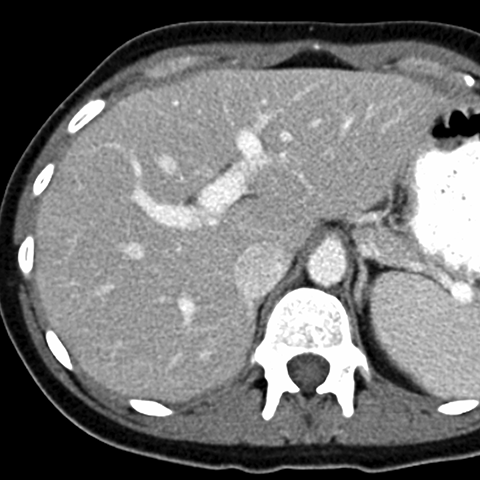

Normal Liver, CT ( axial ) [4 of 9]